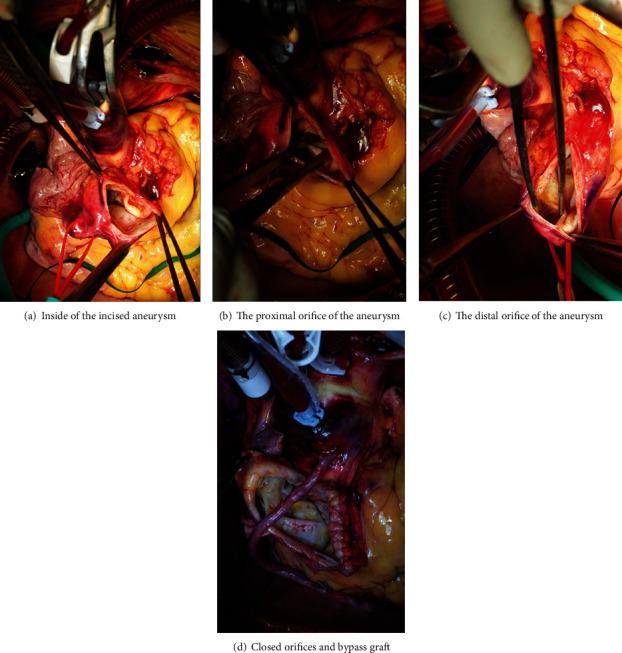

Coronary artery aneurysms combined with left ventricular fistulas are rare; coronary revascularization strategy after coronary artery aneurysm resection is complex in such cases. We report the surgical repair of a giant right coronary artery aneurysm with a fistula in the left ventricle in a 79-year-old woman diagnosed with an aneurysm 50 mm in diameter. Surgical repair included resection of the coronary artery aneurysm, coronary artery bypass grafting to the posterior descending artery, and isolation of reconstructed right coronary circulation from the fistula. The postoperative course was uneventful; postoperative coronary angiography revealed a patent bypass graft unconnected to the left ventricle.

冠状动脉瘤合并左心室瘘极为罕见;在此类病例中,冠状动脉瘤切除术后的冠状动脉血运重建策略十分复杂。我们报告了一例79岁女性患者的手术修复情况,该患者患有直径50毫米的巨大右冠状动脉瘤并伴有左心室瘘。手术修复包括切除冠状动脉瘤、向后降支动脉进行冠状动脉搭桥以及将重建的右冠状动脉循环与瘘管隔离。术后过程顺利;术后冠状动脉造影显示旁路移植血管通畅,未与左心室相连。